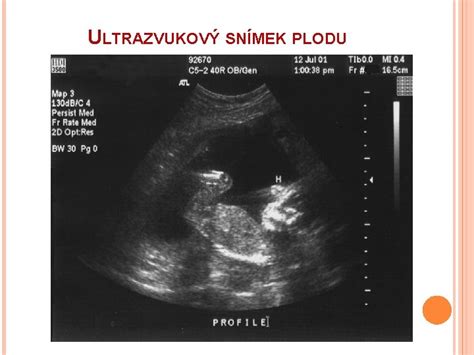

Presné určenie začiatku tehotenstva je kľúčové pre sledovanie jeho priebehu. Lekári zvyčajne používajú tzv. gestačný vek, ktorý sa počíta od prvého dňa poslednej menštruácie. Hoci v tomto momente žena ešte nie je tehotná, tento spôsob počítania je štandardizovaný a umožňuje presné stanovenie predpokladaného termínu pôrodu. Celková dĺžka tehotenstva je v priemere 280 dní, čo zodpovedá 40 týždňom alebo desiatim lunárnym mesiacom. Termín pôrodu sa určuje kombináciou dátumu poslednej menštruácie a ultrazvukového vyšetrenia, často okolo 13. týždňa tehotenstva.

Počas druhého trimestra je dôležité nezabudnúť na registráciu do pôrodnice, ktorá sa môže vyžadovať už od 14. týždňa. Medzi 20. až 22. týždňom sa vykonáva morfologický ultrazvuk, medzi 24. až 28. týždňom glukózový tolerančný test na tehotenskú cukrovku a v rozmedzí 24. až 30. týždňom je ideálny čas na 3D alebo 4D ultrazvuk.